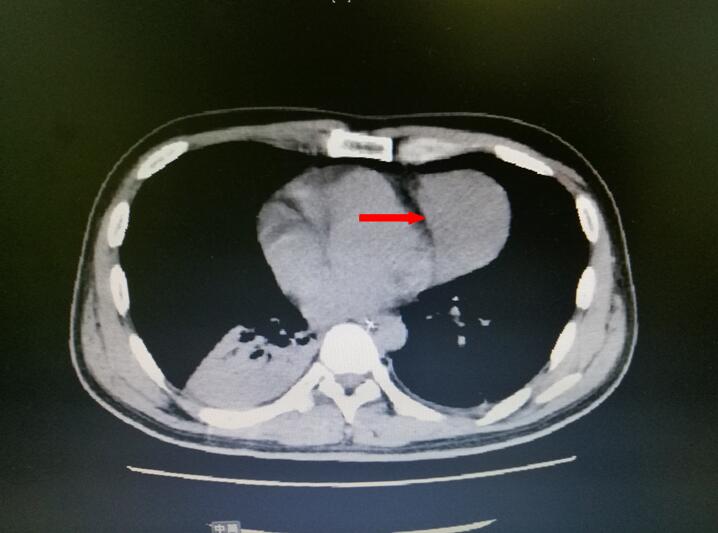

ICU的医疗卫士们详细诊察患者,抽丝剥茧分析病情,发现导致重症肌无力的“根源”——巨大胸腺瘤(见下图箭头处)。而患者肺部氧合情况极差是由于肺部痰液阻塞导致。